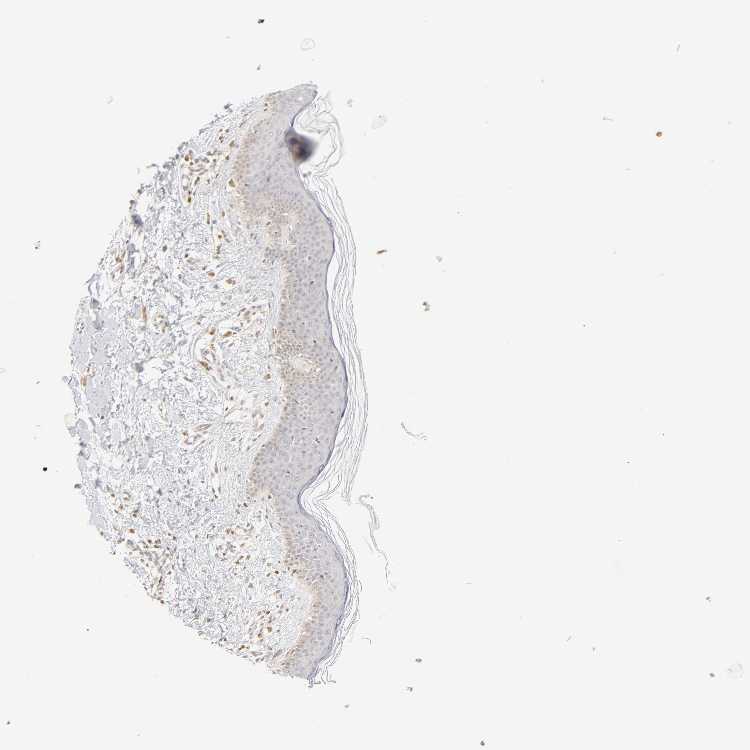

SKIN 1 - Antibody stainingi

Antibody staining in the annotated cell types in the current human tissue is reported as not detected, low, medium, or high, based on conventional immunohistochemistry profiling in selected tissues. This score is based on the combination of the staining intensity and fraction of stained cells.

Each image is clickable and will lead to virtual microscopy that enables deeper exploration of all samples and also displays staining intensity scores, fraction scores and subcellular localization as well as patient and tissue information for each sample.

Antibody HPA004716

Langerhans Low

Fibroblasts Not detected

Keratinocytes Low

Melanocytes Low